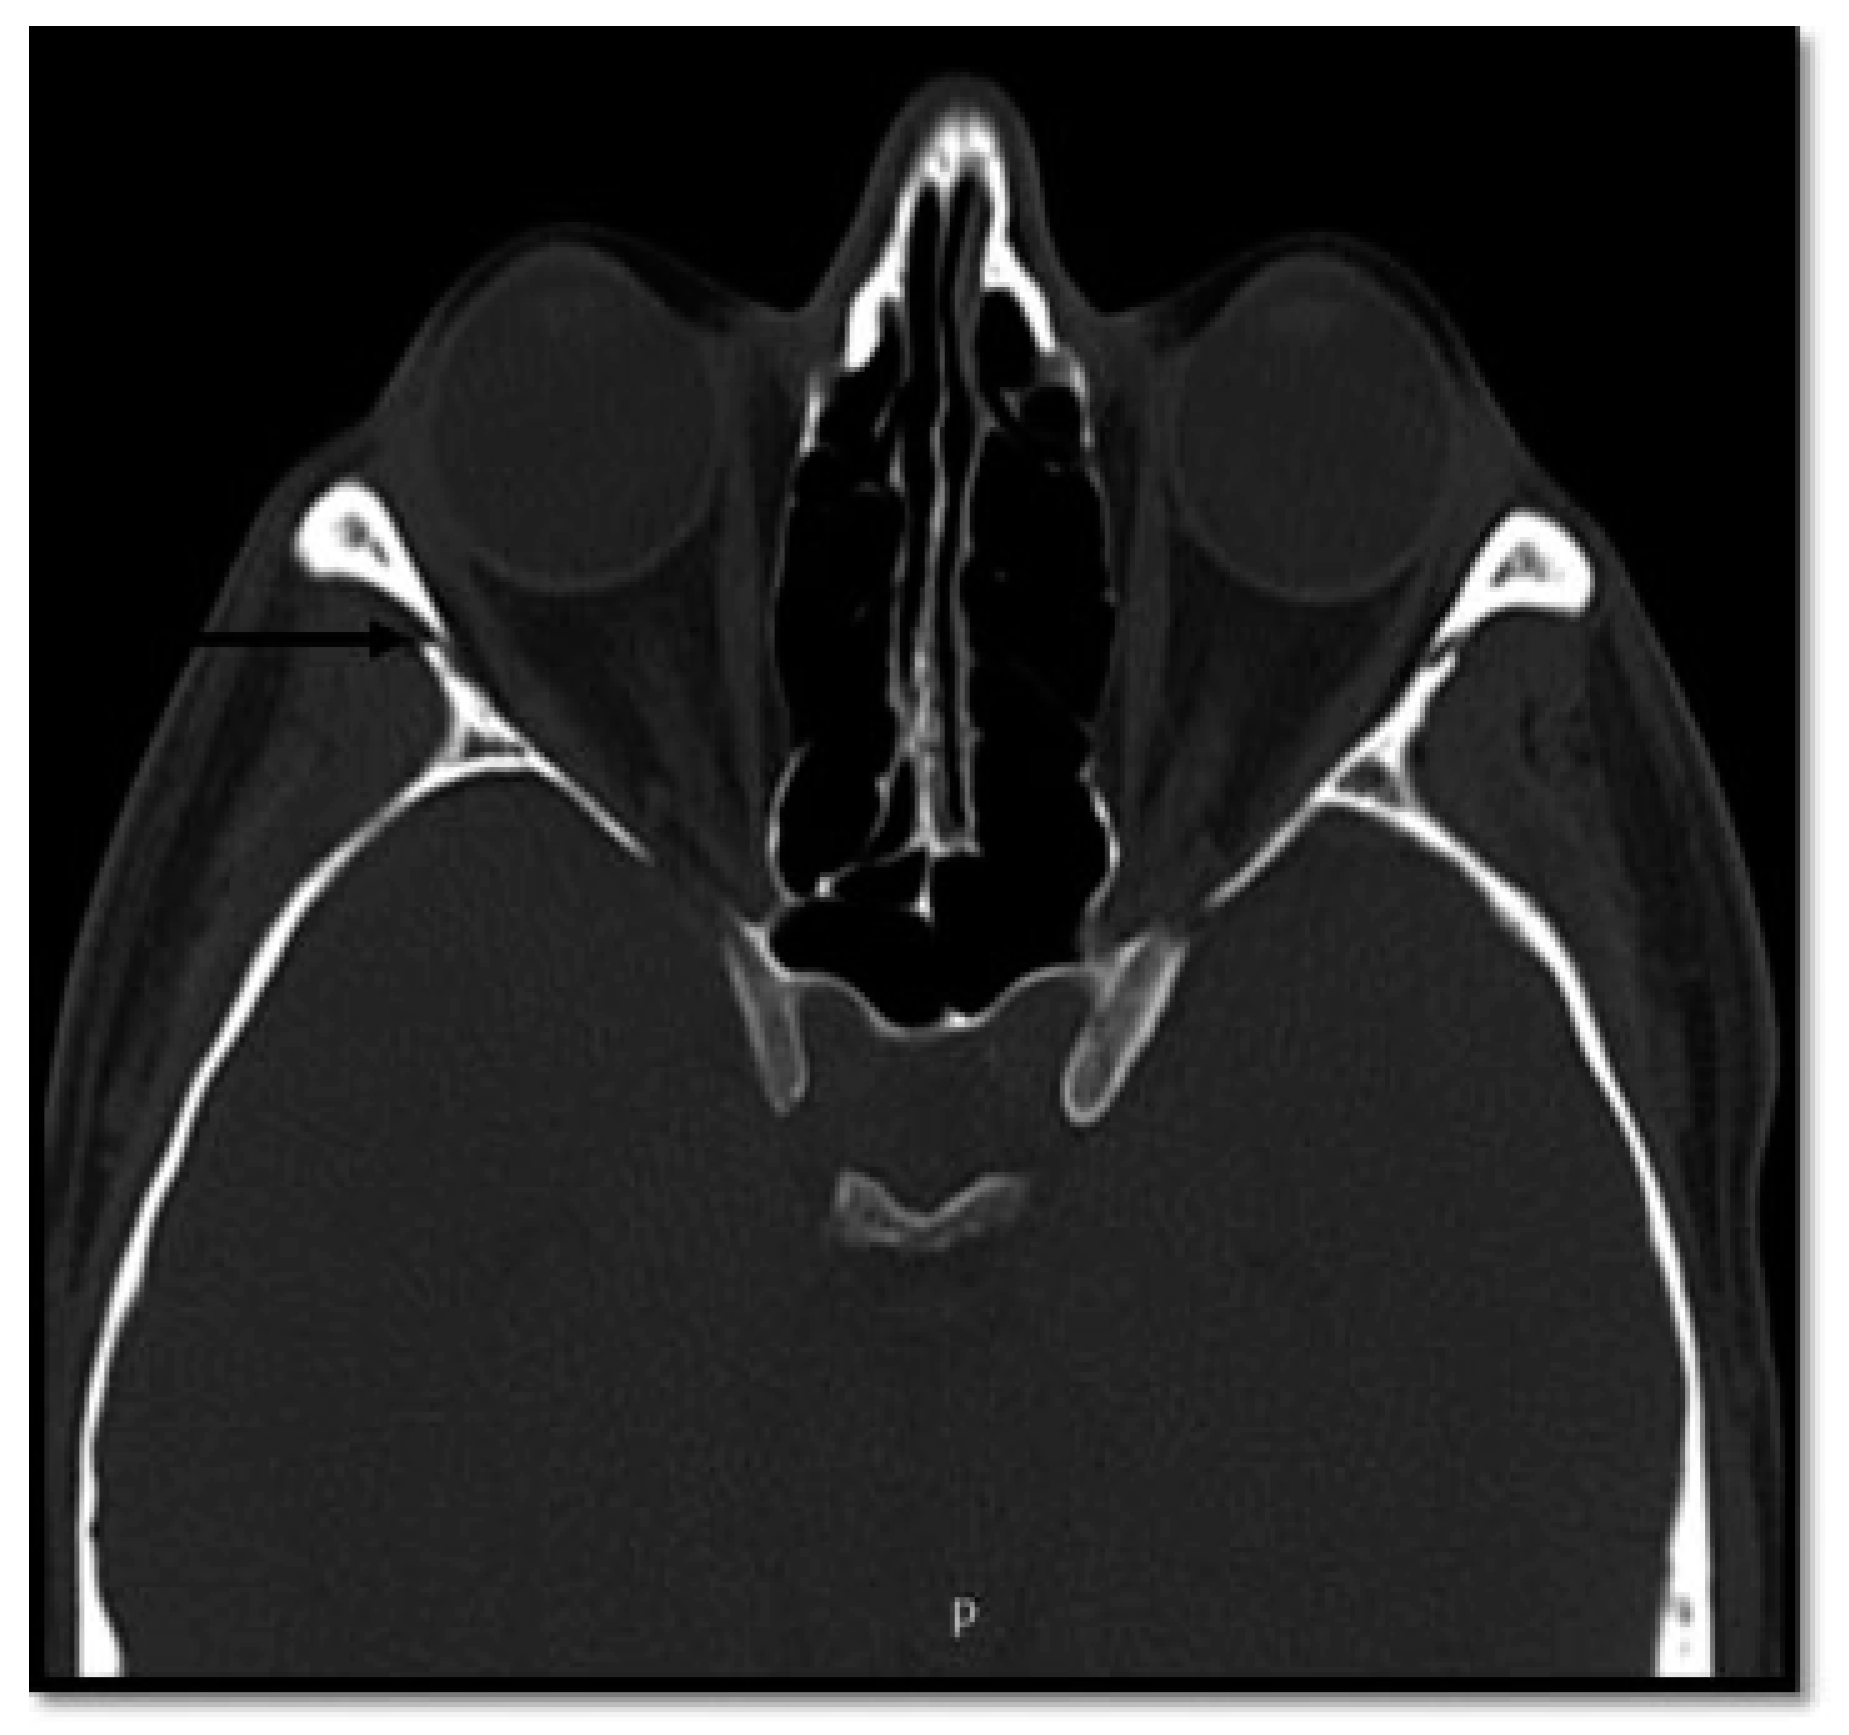

- Additional line extending from the pyriform aperture to the infraorbital rim of the same side (60%).

- Additional line extending from the infraorbital rim to the Le Fort fracture line.

- Additional line extending from the pyriform aperture to the lateral wall of orbit, without breaking the infraorbital rim of the same side (5.4%).

- Additional line extending from the infraorbital rim through the canine fossa to terminate as a fractured dentoalveolar segment of the same side, involving the fractured segment (10.9%).

- Pterygoid plates are not fractured (23.6%).

- D1: Additional Line Extending from the Pyriform Aperture to the Infraorbital Rim of the Same Side (34.5%)

- D2: Additional Line Extending from Infraorbital Rim to the Le Fort Fracture Line (25.4%)

- D3: Additional Line Extending from Pyriform Fossa to Lateral Wall of Orbit, without the Fracture of the Infraorbital Rim of the Same Side (5.4%)

- D4: Additional Line Running from the Infraorbital Rim through the Canine Fossa to Terminate as a Fractured Dentoalveolar Segment of the Same Side (10.9%)

- D5: Pterygoid Plates Are Not Fractured (23.6%)